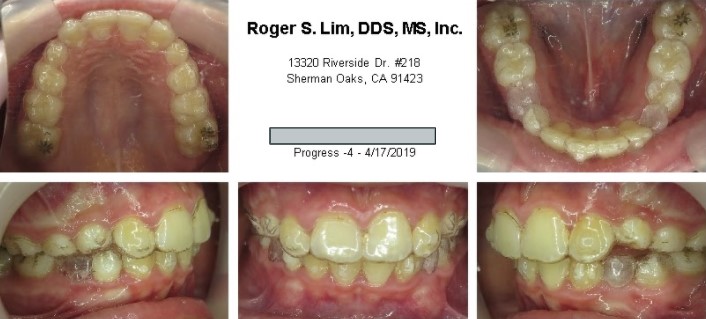

During orthodontics

After Orthodontics & Bridges